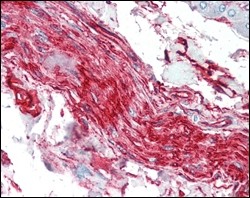

S100A10/P11 Primary Antibody MP20120 [M4E7E10]

| IHC | 1/200 - 1/400 |